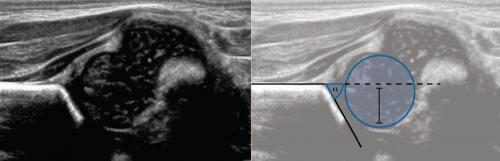

По результатам УЗИ у 286 (72,41%) детей диагностированы типы 1а и 1б тазобедренных суставов (по Г. Рейнгарду). Клинически и сонографически типы 1а и 1б соответствуют возрасту ребенка - это здоровые суставы. Костная часть вертлужной впадины хорошо определяется, костный эркер слегка сглажен или прямоугольный, хрящевая часть крыши охватывает головку бедренной кости, костно-хрящевое соотношение больше или равно 2/3. Угол α больше или равен 60°. Угол β меньше 55° - тип 1а (рис. 1); угол β больше 55° - тип 1б.

Младенец лежит на спине или на боку. Бедро оценивают в нейтральном (15-20°) и согнутом (90°) положениях. Линейный датчик 7-15 МГц располагают в проекции большого вертела параллельно (1) или перпендикулярно (2) поясничному отделу позвоночника.

На первом этапе тазобедренный сустав сканируют в продольной плоскости. Проводят основные линии, измеряют костное покрытие головки, расстояние от лобковой кости до головки, ∠α и ∠β, а также определяют тип строения по Графу.

Пока головка бедренной кости хрящевой плотности, имеется акустическое окно для исследования вертлужной впадины. При продольном сканировании документируют по два снимка: первый — обзорный, второй — с линиями и углами.

Линии костной (красная) и хрящевой (зеленая) крыши проходят через костный выступ, а так же начало Y-хряща и центр гиперэхогенного кончика суставной губы, соответственно. Степень развития костной крыши определяет ∠α, а хрящевой крыши ∠β.